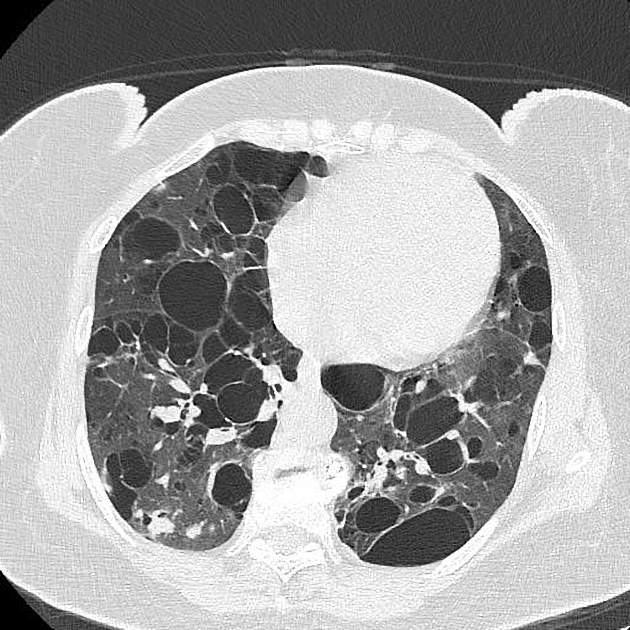

■ Fibrotic changes (섬유성 변화)

§ Lower lobe fibrotic change

- Idiopathic pulmonary fibrosis (IPF)

→ 흔한 하엽 섬유성 변화의 원인으로, honeycombing 이 특징